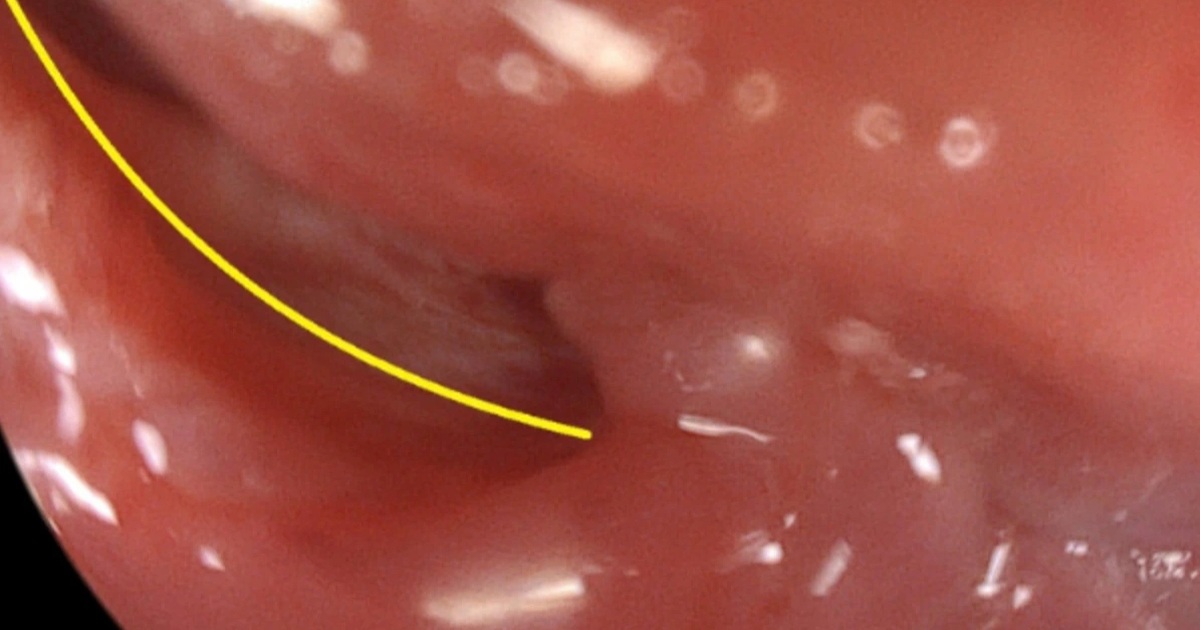

Kết quả nội soi dạ dày cho thấy tổn thương thực quản của bệnh nhân (Ảnh: BV)

Qua quá trình thăm khám và thực hiện các xét nghiệm cần thiết, các bác sĩ phát hiện bệnh nhân bị rách thực quản đoạn 1/3 trên với đường kính vết rách lên tới 7mm. Kết quả chụp CT lồng ngực cũng cho thấy tình trạng tràn khí trung thất và tổn thương mô mềm vùng cổ.